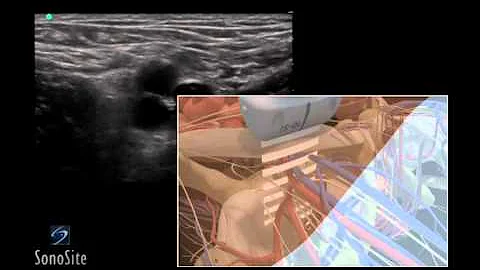

How To: Ultrasound Guided Insertion Internal Jugular Catheter (long) 3d Video

Visit http://www.sonosite.com/education for more videos like this one. Using 3D animations we have come up with a new way of ...